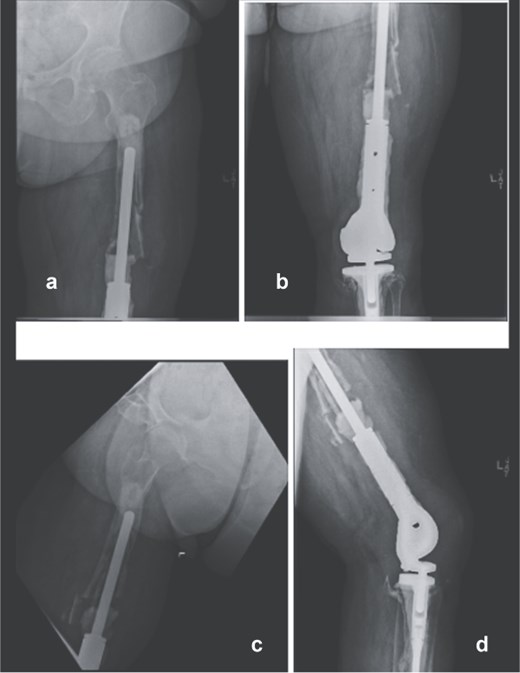

Following implant removal and thorough debridement, a custom total femur antibiotic spacer was fashioned using an Ilizarovrod embedded in antibiotic-loaded cement, coupled to a fully cement-coated fusion nail (Fig. 2). This construct extended from the acetabulum to the tibia, preserving limb length and joint space. The patient was kept non-weight-bearing and initiated on intravenous cefazolin. The postoperative course was uneventful, with no immediate complications.

Intraoperative anteroposterior radiographs (e and f) after stage one, demonstrating a custom antibiotic-loaded total femur spacer constructed using an Ilizarov rod embedded in antibiotic cement and a fully cement-coated fusion nail extending from the acetabulum to the tibia. The resected right femoral implant is grossly visualized (g) prior to spacer placement.